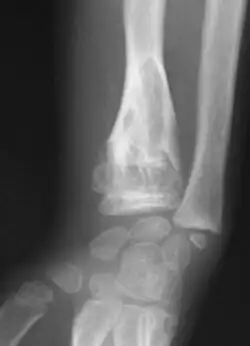

| X-ray image showing enchondromas localized in the lower part of the radius of a 7-year-old girl with Ollier disease. | |

Abnormal bone growth such as shortening or thickening and deformity may be observed in patients of Ollier disease. These bone lesions are visible at birth using radiography but are usually not screened or examined for until clinical manifestations present during early childhood. However, some patients may exhibit no signs of any symptoms.[1] One study found thirteen to be the mean age of diagnosis in patients with Ollier disease. In an X-ray, there would normally be the presence of several homogeneous lesions of an oval or elongated shape with bone edges that are slightly thickened.[3] With age, these lesions may calcify and appear as diffusely minute spots or stippled. Fan-like septations or streaks would be indicative of the presence of several enchondromas. Early detection and consistent and repeated monitoring is important in order to prevent and treat any potential bone neoplasms.

X-ray showing enchondromas localized in the lower part of the radius of a 37-year-old patient affected with Ollier disease -